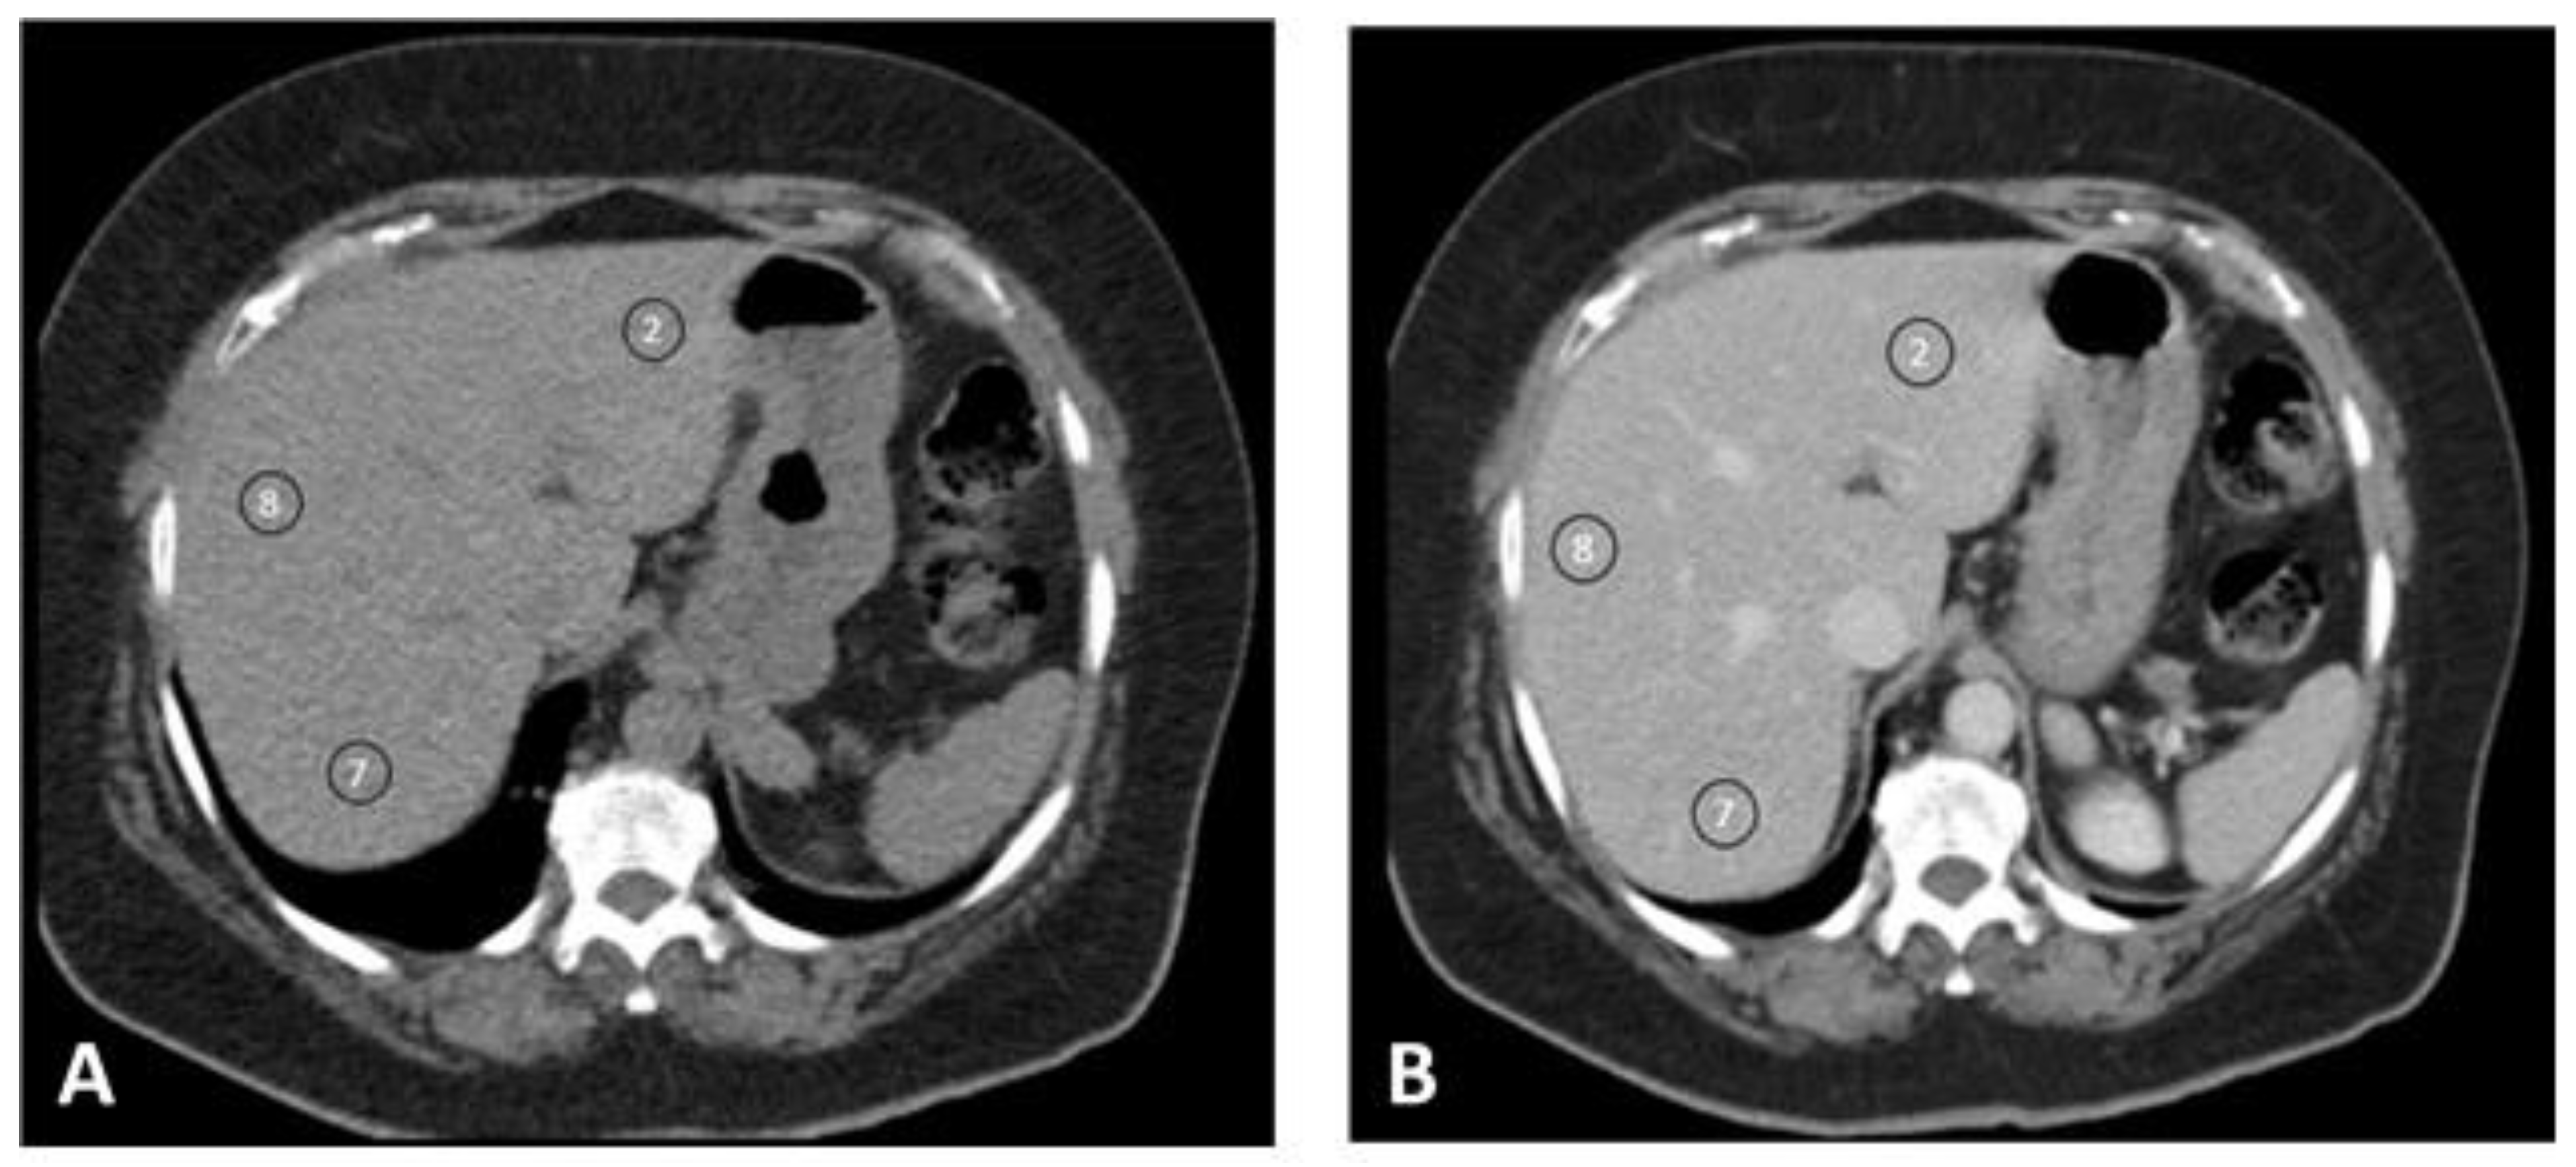

| S2 blanco | 60.5 (±5.77) | 56.7 (±5.02) | 53.6 (±6.30) | 56.8 (±5.83) | 0.000 |

| S2 PV | 120.6 (±11.6) | 109.8 (±11.7) | 105.7 (±9.86) | 111.1 (±12.3) | 0.000 |

| S2 SD | 9.57 (±1.43) | 11.1 (±1.89) | 12.1 (±1.91) | 11.0 (±1.92) | 0.000 |

| Δ S2 | 60.0 (±10.6) | 53.1 (±10.7) | 52.1 (±6.73) | 54.3 (±10.3) | 0.014 |

| S8 blanco | 60.7 (±5.24) | 55.7 (±5.84) | 51.0 (±6.61) | 55.7 (±6.61) | 0.000 |

| S8 PV | 120.9 (±14.2) | 109.2 (±10.9) | 104.4 (±9.52) | 110.5 (±12.5) | 0.000 |

| S8 SD | 9.19 (±0.981) | 10.2 (±1.47) | 11.2 (±2.18) | 10.3 (±1.75) | 0.000 |

| Δ S8 | 60.1 (±12.6) | 53.5 (±10.8) | 53.4 (±8.18) | 54.8 (±10.9) | 0.043 |

| S7 blanco | 59.5 (±5.56) | 54.5 (±5.35) | 50.8 (±6.82) | 54.7 (±6.32) | 0.000 |

| S7 PV | 118.7 (±10.8) | 107.8 (±10.1) | 103.1 (±8.34) | 109.0 (±11.1) | 0.000 |

| S7 SD | 9.29 (±1.10) | 10.6 (±1.70) | 12.2 (±2.35) | 10.7 (±2.09) | 0.000 |

| Δ S7 | 60.1 (±12.6) | 53.3 (±9.25) | 52.4 (±7.45) | 54.3 (±9.30) | 0.022 |

| Δ S2 Δ S8 Δ S7 | 0.667 | 0.939 | 0.520 | 0.114 | |

| Mean Δ | 60.7 (±12.4) | 53.3 (±9.75) | 52.6 (±6.63) | 54.6 (±10.2) | 0.007 * |